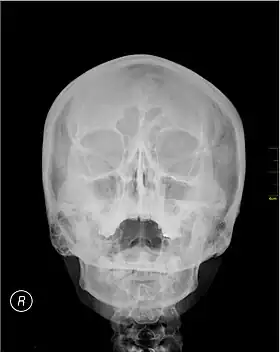

Waters' view

Waters' view (also known as the occipitomental view or parietoacanthial projection) is a radiographic view of the skull. It is commonly used to get a better view of the maxillary sinuses. An x-ray beam is angled at 45° to the orbitomeatal line. The rays pass from behind the head and are perpendicular to the radiographic plate. Another variation of the waters places the orbitomeatal line at a 37° angle to the image receptor. It is named after the American radiologist Charles Alexander Waters.

Structures observed

Waters' view can be used to best visualise a number of structures in the skull.

- Maxillary sinuses.

- Frontal sinuses, seen with an oblique view.

- Ethmoidal cells.

- Sphenoid sinus, seen through the open mouth.

- Odontoid process, where if it is just below the mentum, it confirms adequate extension of the head.